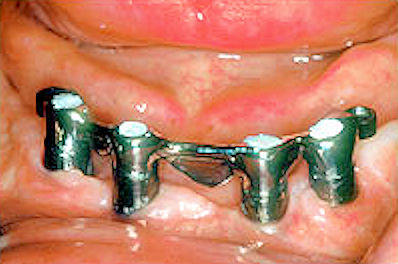

At this point, the metal bar is placed on the abutments. You will have the first try-in of your new denture framework to see if it fits properly.

Bar secured to abutment with screws